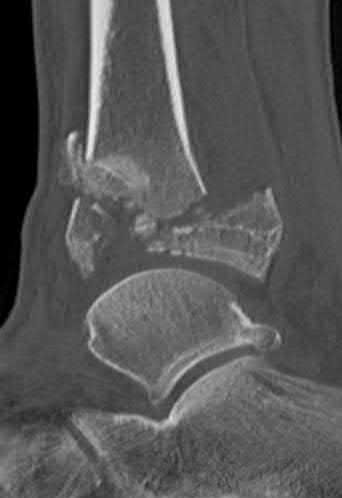

A 28-year-old male sustains a severe hyper-dorsiflexion injury to his ankle in a motor vehicle accident, resulting in a Hawkins Type III talar neck fracture. Which of the following arteries provides the predominant blood supply to the body of the talus, placing it at significant risk for avascular necrosis in this injury?

Explanation

The artery of the tarsal canal, which is a branch of the posterior tibial artery, provides the dominant blood supply to the talar body. In a Hawkins Type III fracture (talar neck fracture with subtalar and tibiotalar dislocation), the blood supply from the artery of the tarsal canal, the artery of the sinus tarsi, and capsular vessels are disrupted, leading to an avascular necrosis (AVN) rate approaching 100%.